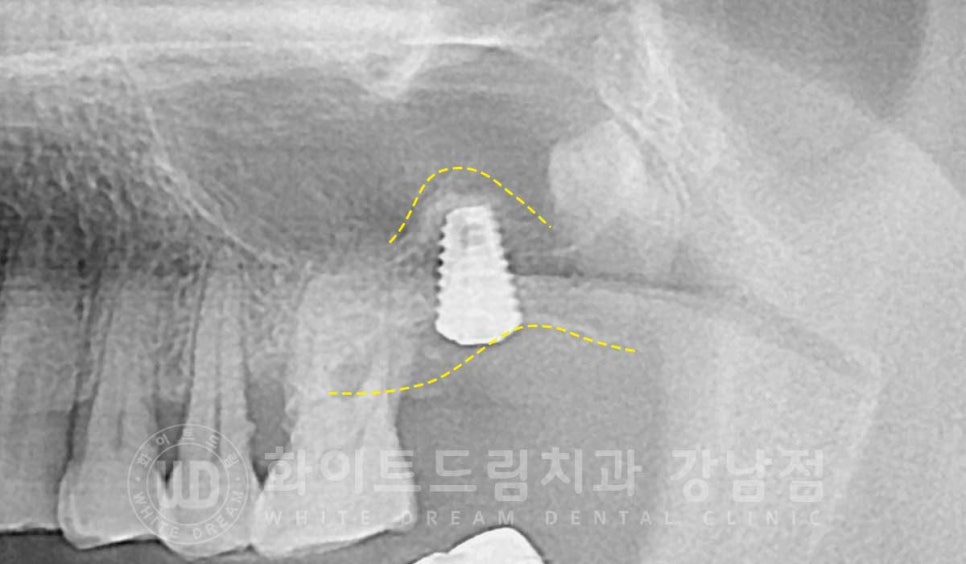

상악동 거상술을 진행하면 X-RAY 상에서 임플란트 위쪽으로 둥근 돔 형태를 확인할 수 있습니다.

상악동이 예쁘게 잘 들어 올렸다는 것을 의미하고

시간이 지난 후 수술 부위가 아물고, 새로운 뼈가 잘 형성이 되면

이렇게 뼈이식 위쪽으로 하얗게 치밀골이 형성되어 있는 것이 확인된답니다.